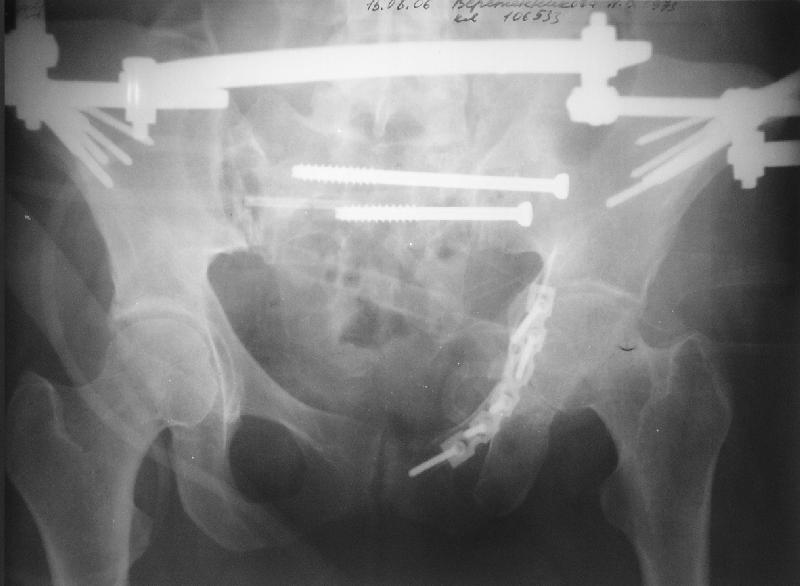

Прооперировали молодую девушку 32 лет спустя 9 мес после травмы.

Имелся стойкий болевой синдром, неопороспособность левой н/конечности, моторные и сенсорные нарушения в левой голени и стопе, патологическая подвижность левой половины таза. Первым этапом закрыто в аппарате исправили деформацию ( в течении 2,5 нед). Вторым закрытое введение илиосакральных винтов в крестец (канюллированные 7,2 мм Chm) + туннелизация зоны псевдоартроза спицама Киршнера, реконструкция передних отделов таза, накостный остеосинтез . Аппарат частично демонтирпован, оставлена "передняя рама" После устранения деформации отмечен регресс неврологической симптоматики, уменьшение болевого синдрома. Интересующие вопросы: 1. Прогноз для сращения псевдоартроза крестца. 2. сроки нагрузки весом левой половины таза. Буду очень признателен за ваши мнения по этому поводу.A female 32 y.o. admitted to our unit 9 months after initial injury with pain, inability to bear weight at the left lower limb, sensor and motor disturbances in the left foot and tibia, with mobility of the left hemipelvis.At first closed reduction was performed by an external fixator within 2,5 weeks. After correction her pain decreased and some neurological progress was achieved. Now two iliosacral screws 7,2 mm were inserted, and anterior lesion was fixed by a plate. External fixator was partially unmounted, only anterior frame left in place.Images attached.How would you evaluate chances of healing of the sacrum with the current position?When would you allow weight-bearing of the left leg?THX in advance.

Мне нравится ваша закрытая репозиция девятимесячного ложного сустава, не знаю насчет туннелизации, но шурупы в 7.2 это серёзная конструкция. При стабильной фиксации крестец должен срастись, только я бы держал передний фиксатор до шести недель, костыли, а полную нагрузку разрешить через 12 недель.